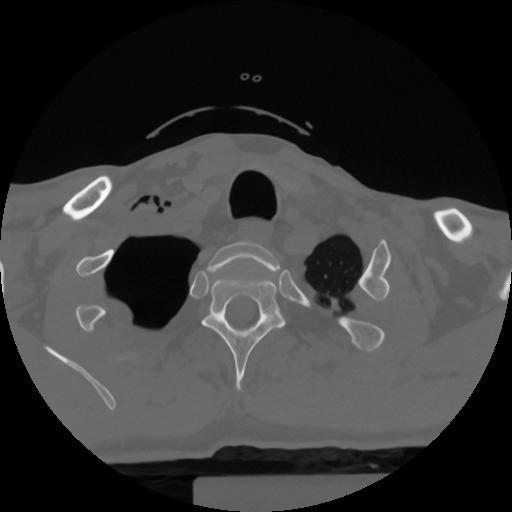

12 P.BLANDAS,,Vol,0.5,P.BLANDAS,,